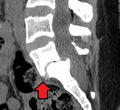

MRI of L5-S1 spondylolisthesis- X-ray of a grade 4 spondylolisthesis at L5-S1 with spinal misalignment indicated